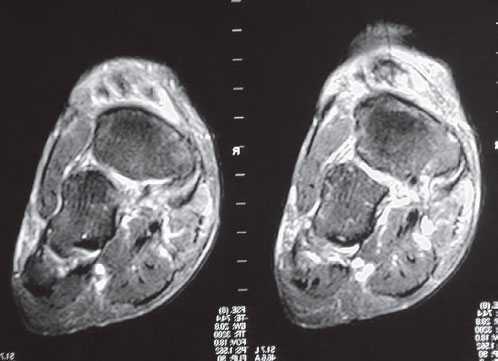

Магнитно-резонансную томографию (МРТ). Этот метод позволяет визуализировать мягкотканные структуры, например, мышцы и сухожилия. МРТ назначается в случаях, когда диагноз вызывает сомнения.

Оптимально точной диагностической методикой определения тех или иных патологий сухожилий, на сегодняшний день, является МРТ. Именно МРТ наилучшим образом способствует выявлению целого спектра повреждений и дегенеративных изменений, имеющихся в стопе, а также позволяет отличить наличие воспалительного процесса от разделения сухожилия.